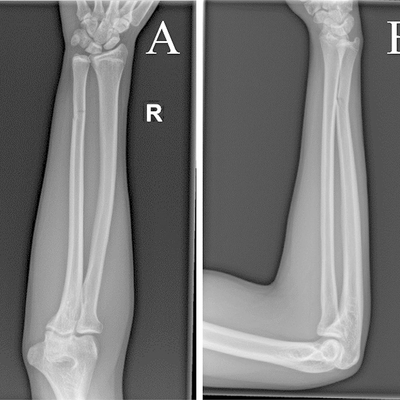

Click on an image below to view more info.